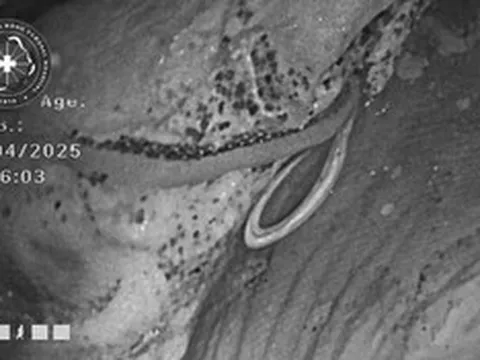

Ê-kip thực hiện ca phẫu thuật.